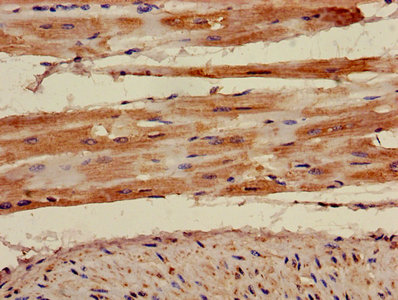

ApplicationELISA, IHC, IF; Recommended dilution: IHC:1:20-1:200, IF:1:50-1:200